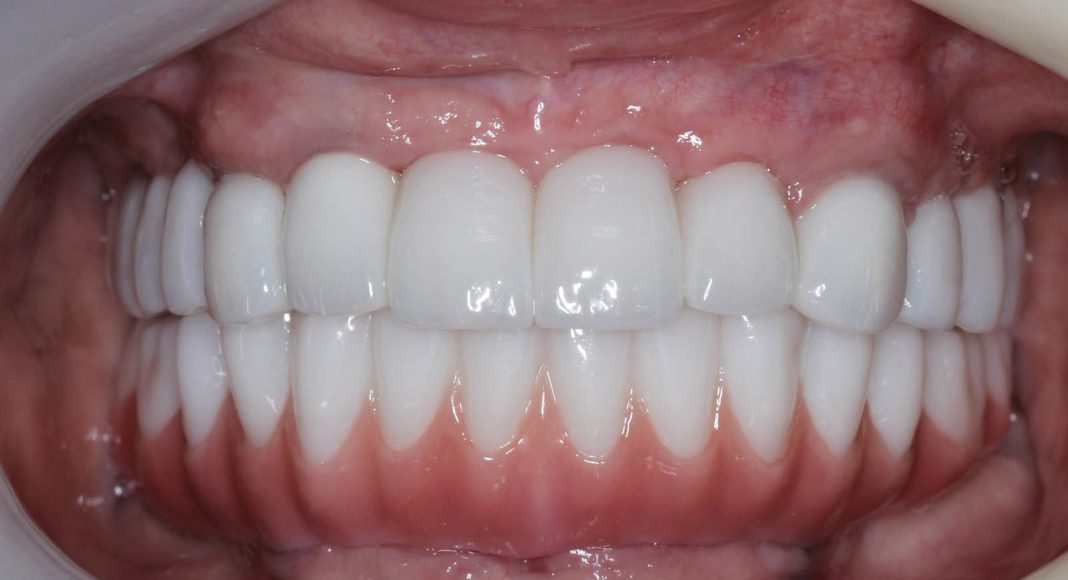

Lips retracted, frontal view with prosthesis. She is a Class 2, deep bite. Note that her lower front teeth are not visible (100% vertical overlap).

Frontal view – upper zirconia bridges with lower acrylic temporary. We are now ready to finish the lower jaw.

Right lateral, mirror view of the upper and lower zirconia bridges. Note the beautiful, healthy tissue response.